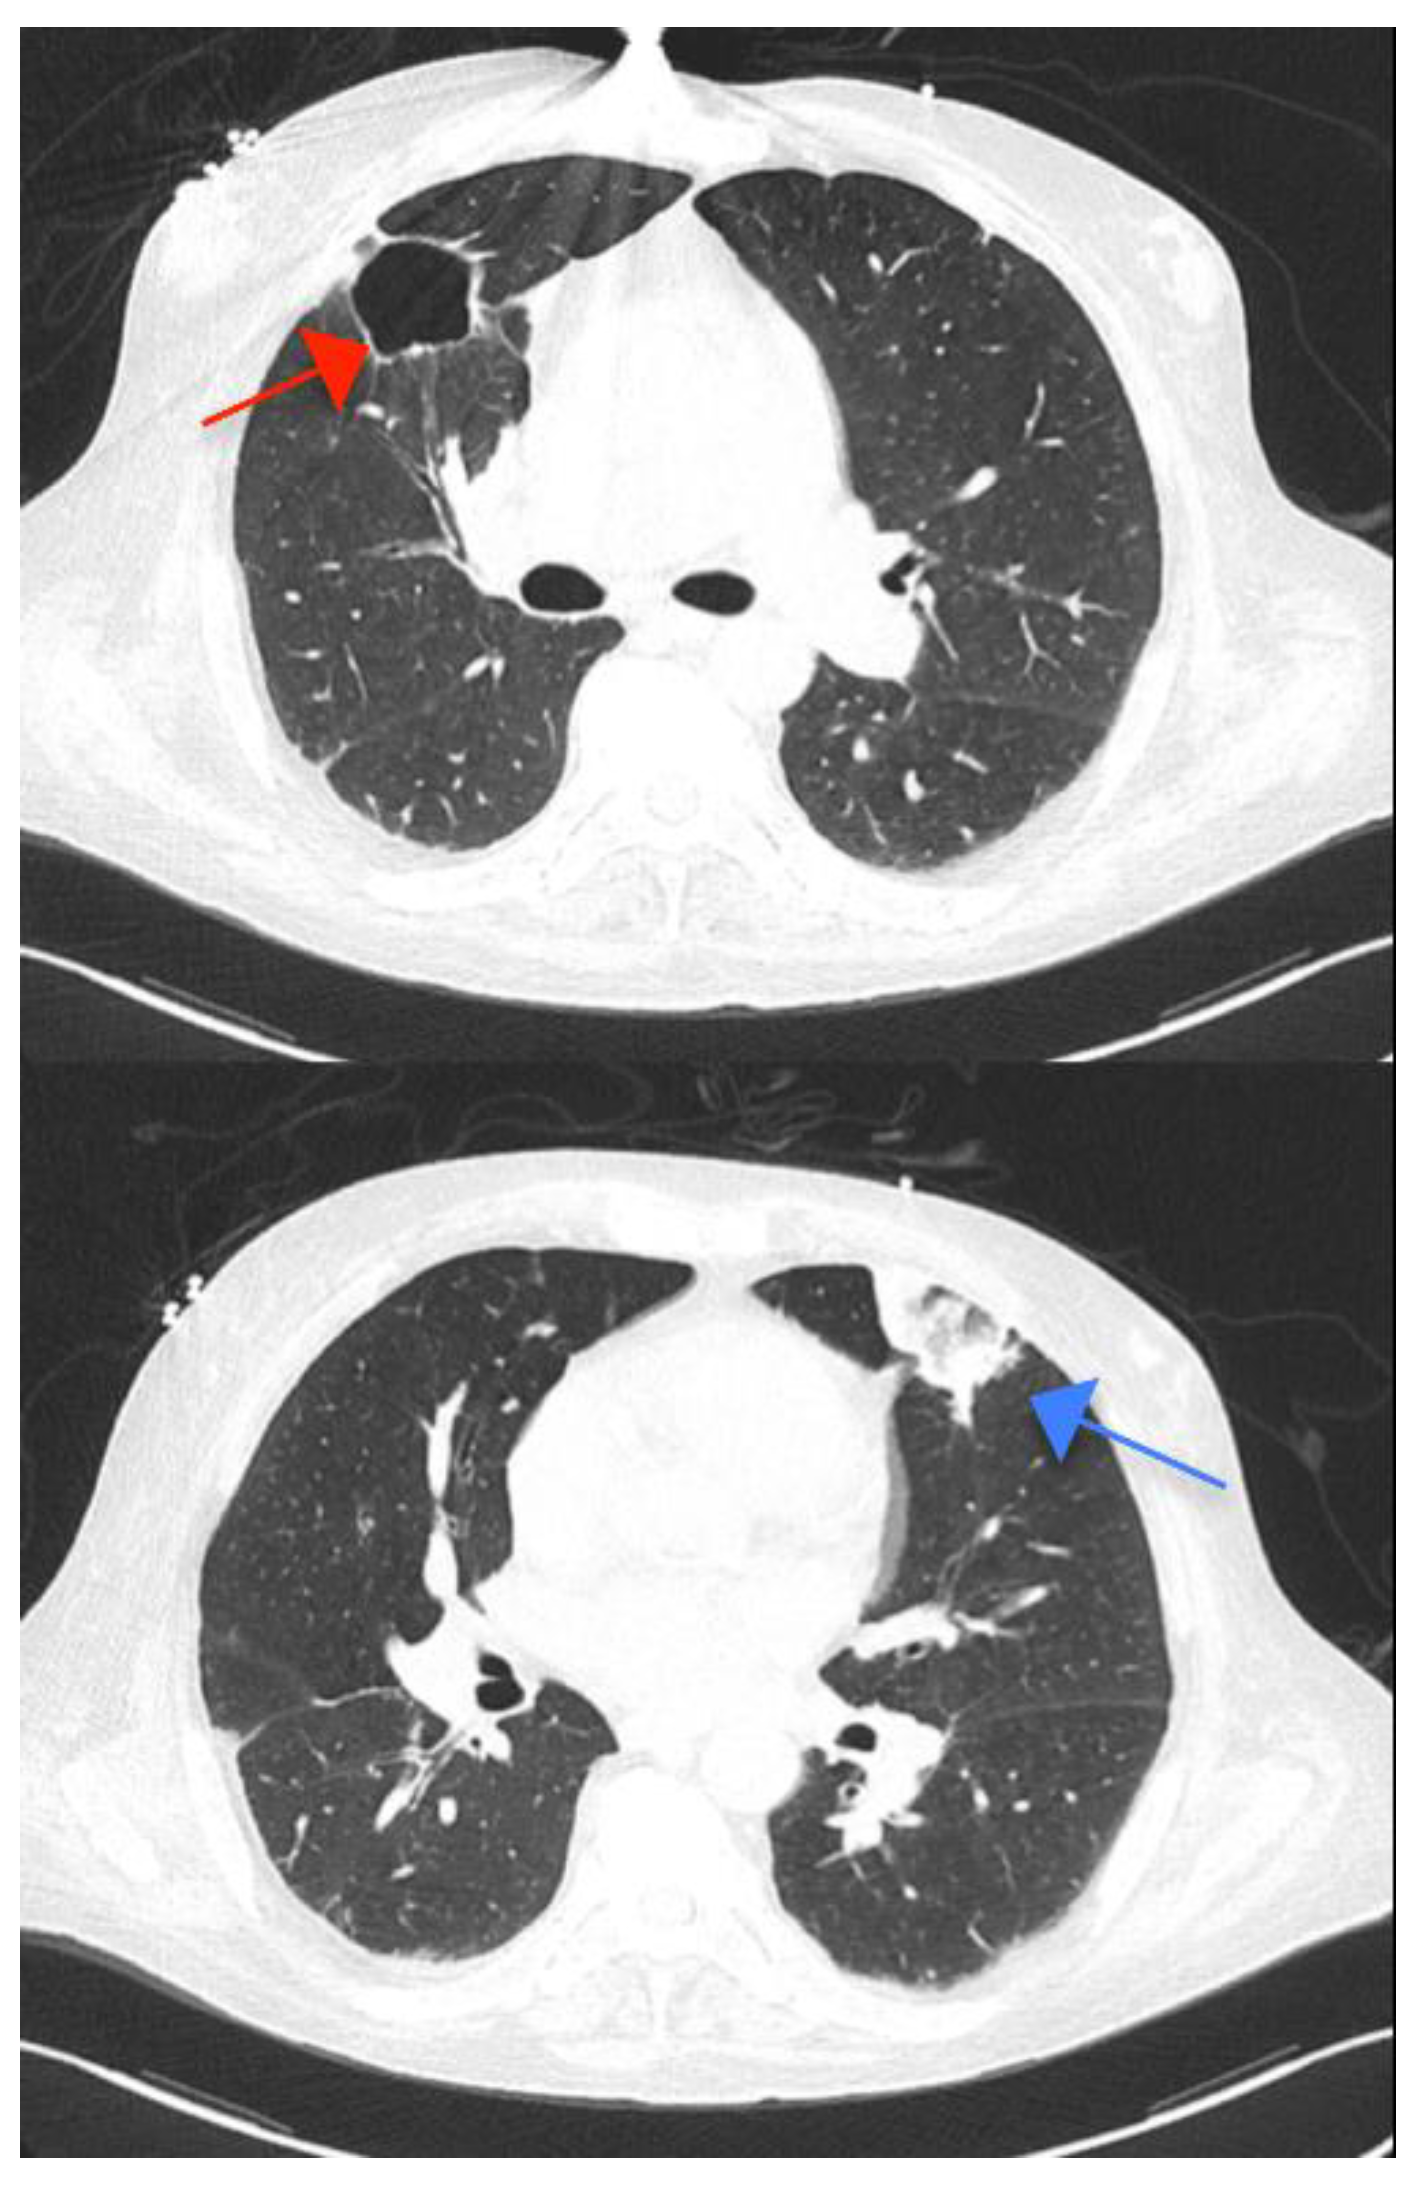

Four cavities in the lungs were identified as tuberculosis sequelae (Figure 5); however, two lobar consolidations raised the possibility of tuberculosis reactivation, which was later excluded by negative sputum smear, presumably indicating embolization from the right-sided IE. Additional coronary CT angiography showed no significant stenosis in the coronary arteries.

Figure 5. Thoracic computed tomography revealing one of the four cavities in the right upper lobe (red arrow) and one triangular consolidation in the left superior lobe, raising the suspicion of tuberculosis reactivation (blue arrow).